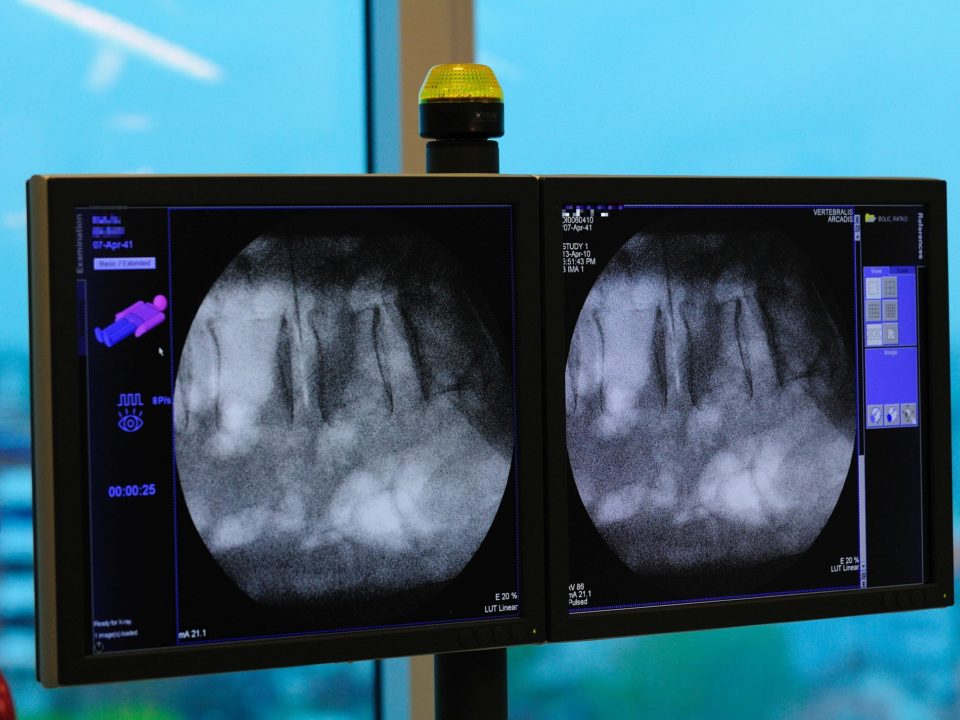

Discography or discogram is a diagnostic method used to determine the structure and damage of the disc(s) as well as to determine whether a particular disc is the generator of pain.